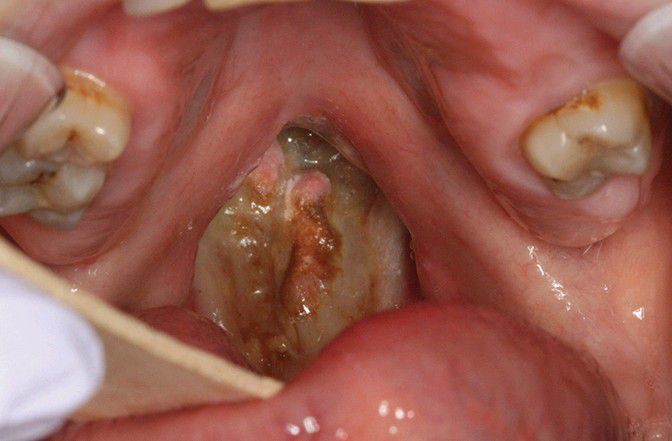

Oxycodone-related Palatal Perforation.

Midline perforation of the palate in abuser of oxycodone.

Palate

Perforation

Oxycodone